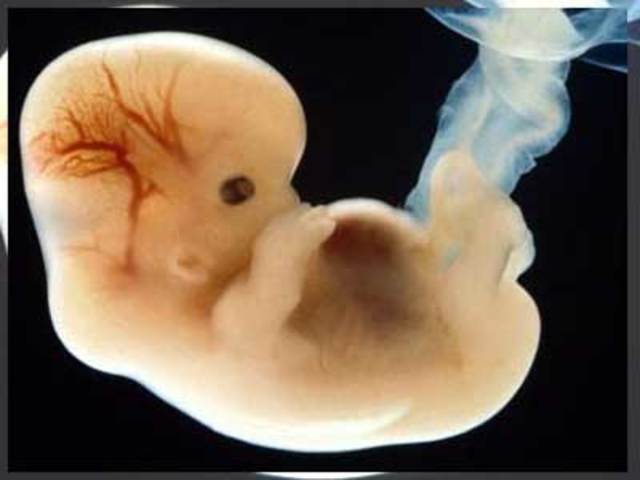

• 8 SEMANA

8 SEMANA

el embrión mide aproximadamente 3cm. La cara adquiere aspecto humano. .Se pueden ver los ojos, nariz y orejas. Loa párpados cubren los ojos. Los labios están divididos en sus segmentos .En los brazos y las piernas se pueden distinguir sus segmentos definitivos, y los dedos están bien formados.